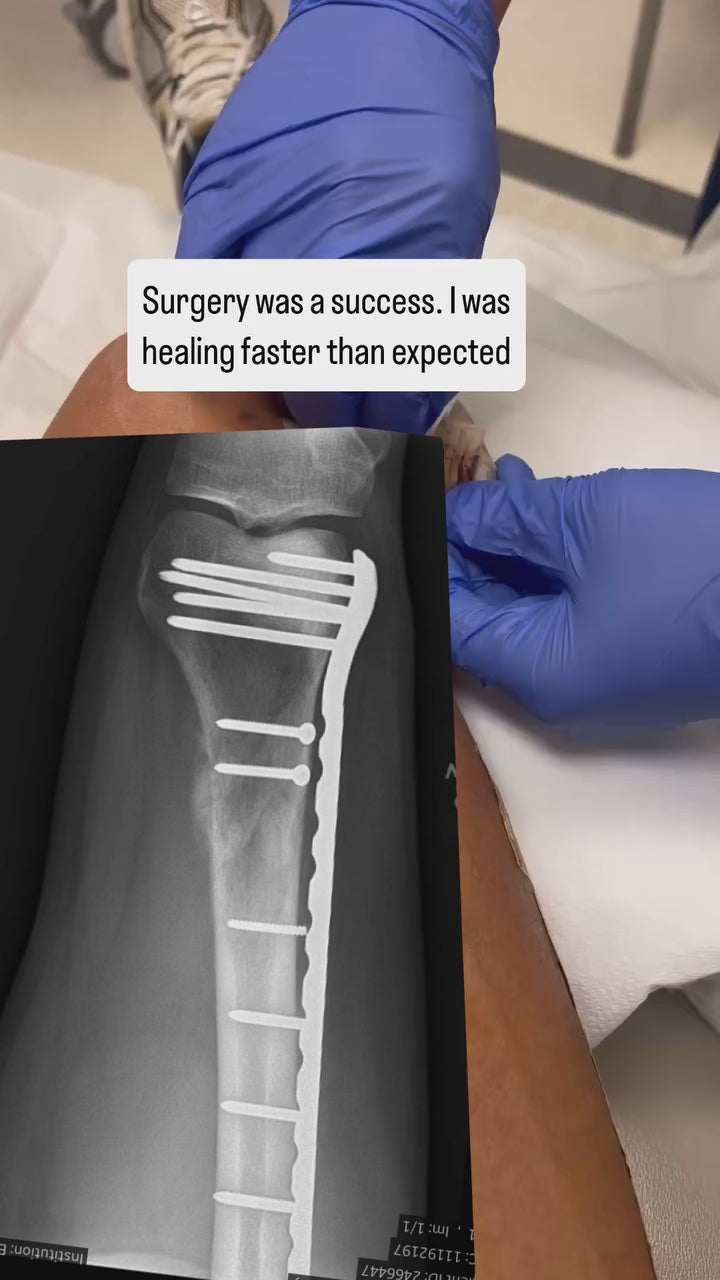

Johan is currently facing a difficult battle with cancer.